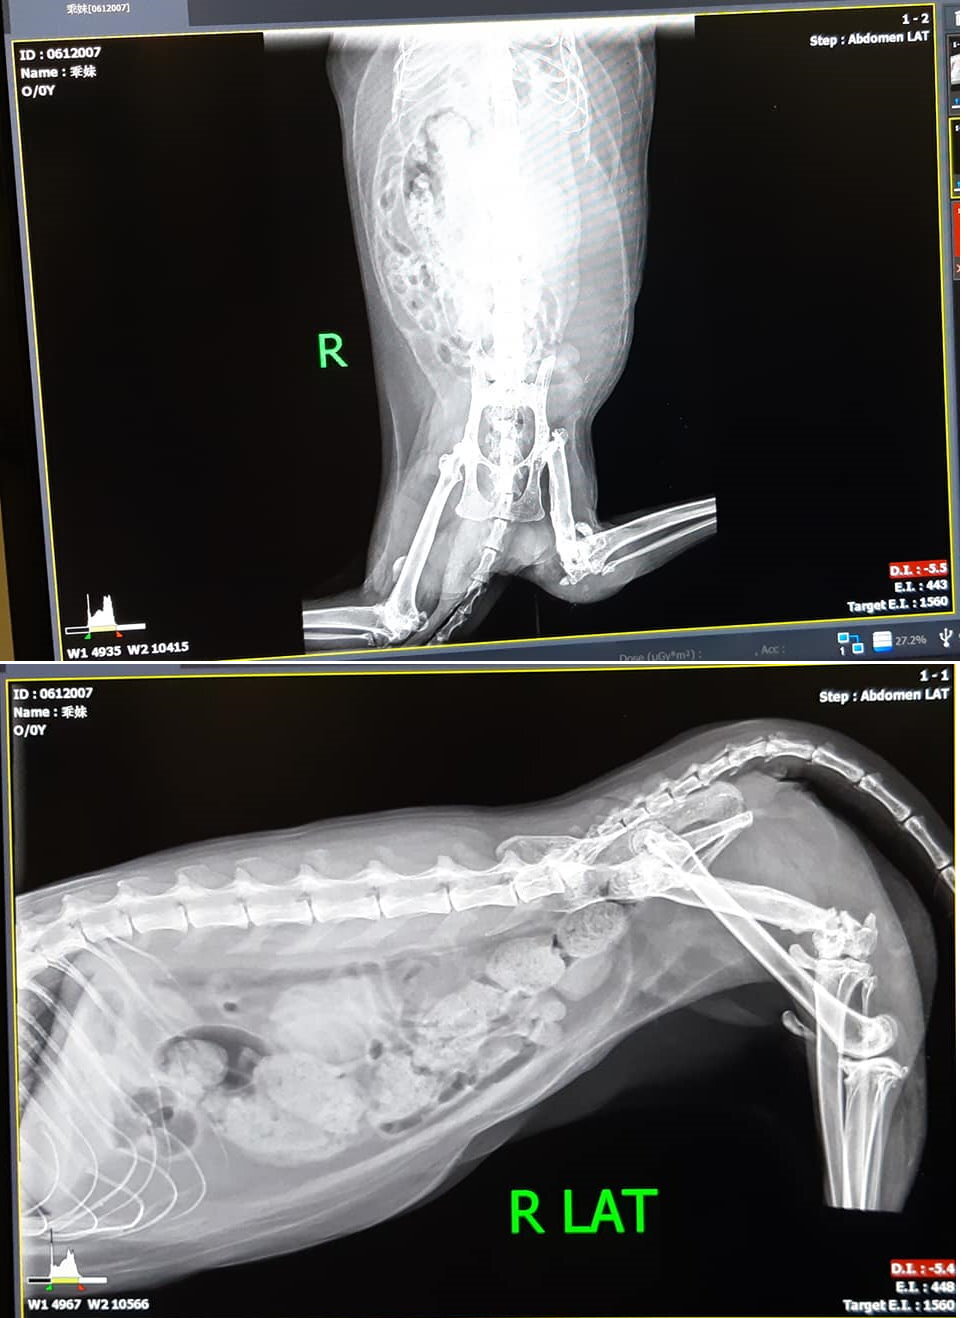

乖妹是為期半年的腎臟檢查,查看有無結石,今進行項目是X光及血檢。

X光檢查,因乖妹在提籠裡尿尿,所以看到的膀胱很小,但確定沒有結石,腎臟也無結石,因此不須再做超音波檢查。

腸道內雖然便便很多,但以形狀看來不到積便程度,應可以自行排出,。

體重較之前手術時的3.8kg變重很多,以癱瘓貓咪來說,須留意不要過胖。